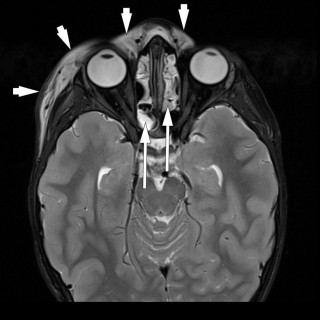

En mann i 50-årene ble innlagt etter residiverende episoder med brystsmerter. På innleggelsesdagen synkoperte han fra sittende stilling. Utredningsforløpet avdekket en diagnose som er sjelden, men med klassiske symptomer og funn. En mann i 50-årene med kjent hypertensjon, velregulert med kandesartan (tabletter, 8 mg × 1), ble henvist til akuttmottaket på grunn av episoder med brystsmerter. Han var normalvektig, hadde aldri røykt og hadde ingen rusbrukslidelse, og det var ingen kjent diabetes, hyperkolesterolemi, opphopning av hjertesykdom eller prematur hjertedød i familien. Over en periode på...